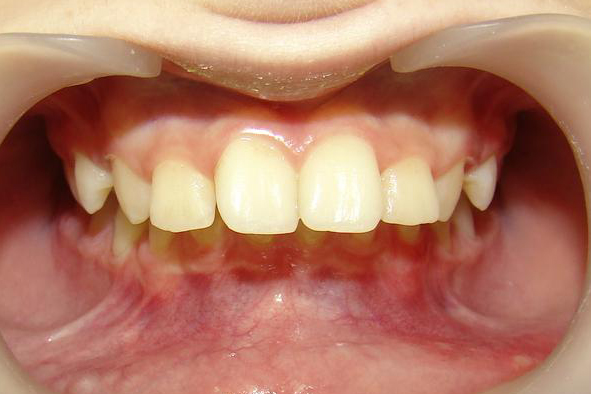

А это уже молодой человек 10 лет. Тоже получилось справиться без удаления. Хоть оно и было показано. Но мальчик очень упорно носил специальные аппаратики и резиночки. Покажу со всех сторон. Этот случай победил в конкурсе на конференции